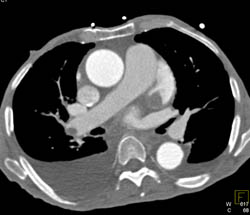

Aneurysm of Left Circumflex Coronary Artery